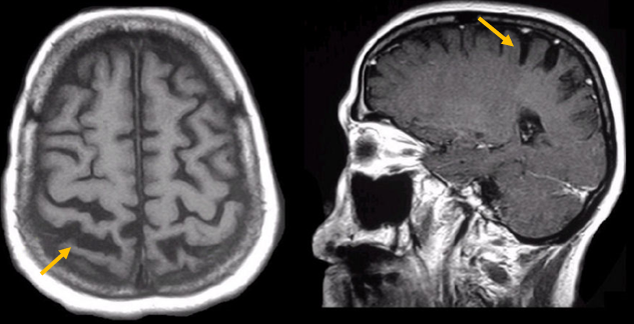

진행 핵상 마비는 대표적인 파킨슨 증후군 중의 하나입니다. 파킨슨병과 다른 점은 질병의 초기부터 중심을 잡기 어려운 체위 불안정이 나타나 자주 넘어진다는 것입니다. 파킨슨병의 경우 질병이 상당히 진행된 뒤에 체위 불안정이 나타납니다. 또한 진행 핵상 마비에서는 목 주위 근육을 비롯한 몸 중심 근육의 경축이 나타나, 목을 뒤로 젖히면서 걷는 모습이 보입니다. 그리고 눈의 운동을 조절하는 기능에 장애가 나타나 아래쪽을 바라보는 데 문제가 생겨 계단을 내려갈 때 어려움을 겪는 경우가 많습니다. 진행 핵상 마비가 의심되는 경우, 뇌 자기공명영상(MRI)에서 중뇌의 위축이 비정상적으로 심하게 나타나는 소견을 확인하거나, 뇌포도당 양전자 단층촬영(PET)에서 전두엽과 중뇌의 대사 기능이 저하된 소견을 확인하여 진단에 참고할 수 있습니다.

[진행핵상마비 환자의 뇌자기공명영상에서 확인되는 중뇌 위축 소견]

피질 기저핵 변성은 비대칭 증상을 두드러지게 보인다는 점에서 파킨슨병과 비슷합니다. 그러나 파킨슨병과 비교해 보았을 때 양측의 차이가 아주 심하게 나타난다는 특징이 있습니다. 질병 초기에 한쪽 손으로 동작을 하거나 계획된 행동을 하는 기능이 현저하게 떨어집니다. 간단한 손가락 모양도 따라 하지 못하는 현상을 보입니다. 또한 의지와 상관없이 제멋대로 움직이는 통제불능 손이 나타날 수 있습니다. 체위 떨림, 경축, 운동 완만과 같은 파킨슨병에서 볼 수 있는 증상들은 피질 기저핵 변성에서도 관찰될 수 있습니다. 또한 집중력 장애, 수행 장애, 이름 대기나 언어의 유창성이 떨어지는 등 전두엽 및 두정엽과 관련된 인지 장애가 나타납니다. 피질 기저핵 변성은 뇌 자기공명영상(MRI)에서 증상의 반대쪽 전두두정엽의 위축 소견이 특징적으로 나타납니다. 뇌포도당 양전자 단층촬영(PET)에서도 전두엽, 뇌기저핵에 비대칭적인 대사 저하의 소견이 보입니다.

[피질기저핵 변성 환자의 뇌자기공명영상에서 확인되는 비대칭 뇌피질의 소견]